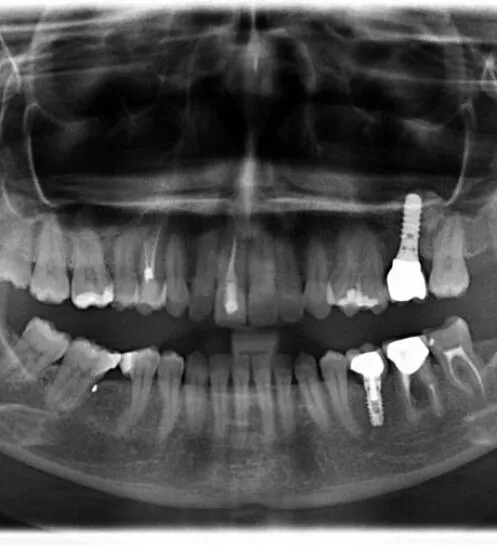

La perdita dei molari superiori lascia in nella maggior parte dei casi una quantità ossea molto ridotta per l’estensione dei seni paranasali (cavità appartenenti al sistema aereo nasale, atte al riscaldamento dell’aria inalata), tale da non permettere l’inserimento impiantare nel modo classico.

Al fine di riabilitare l’elemento dentale perso evitando soluzioni più invasive come protesi mobili o ponti che vanno ad intaccare gli elementi attigui alla perdita dentale è possibile effettuare il posizionamento di un impianto mediante una tecnica di rigenerazione ossea chiamata rialzo di seno mascellare.

–il grande rialzo di seno: permette, in casi in cui l’osso residuo è estremamente ridotto, di ottenere grazie all’inserimento di una maggior quantità di osso sintetico la neoformazione di osso naturale in tempi che variano dagli 8 ai 12 mesi.

–l’approccio crestale che permette l’inserimento immediato dell’impianto con contestuale inserimento di osso sintetico. Questi sono i casi di presenza ossea residua di almeno 4 mm. (tempi di guarigione e di carico variano dai 4 ai 6 mesi)

La scelta deve comunque essere effettuata in base al caso clinico, dopo aver effettuato gli esami radiografici necessari (OPT e/o TAC) e alle condizioni di salute del paziente.